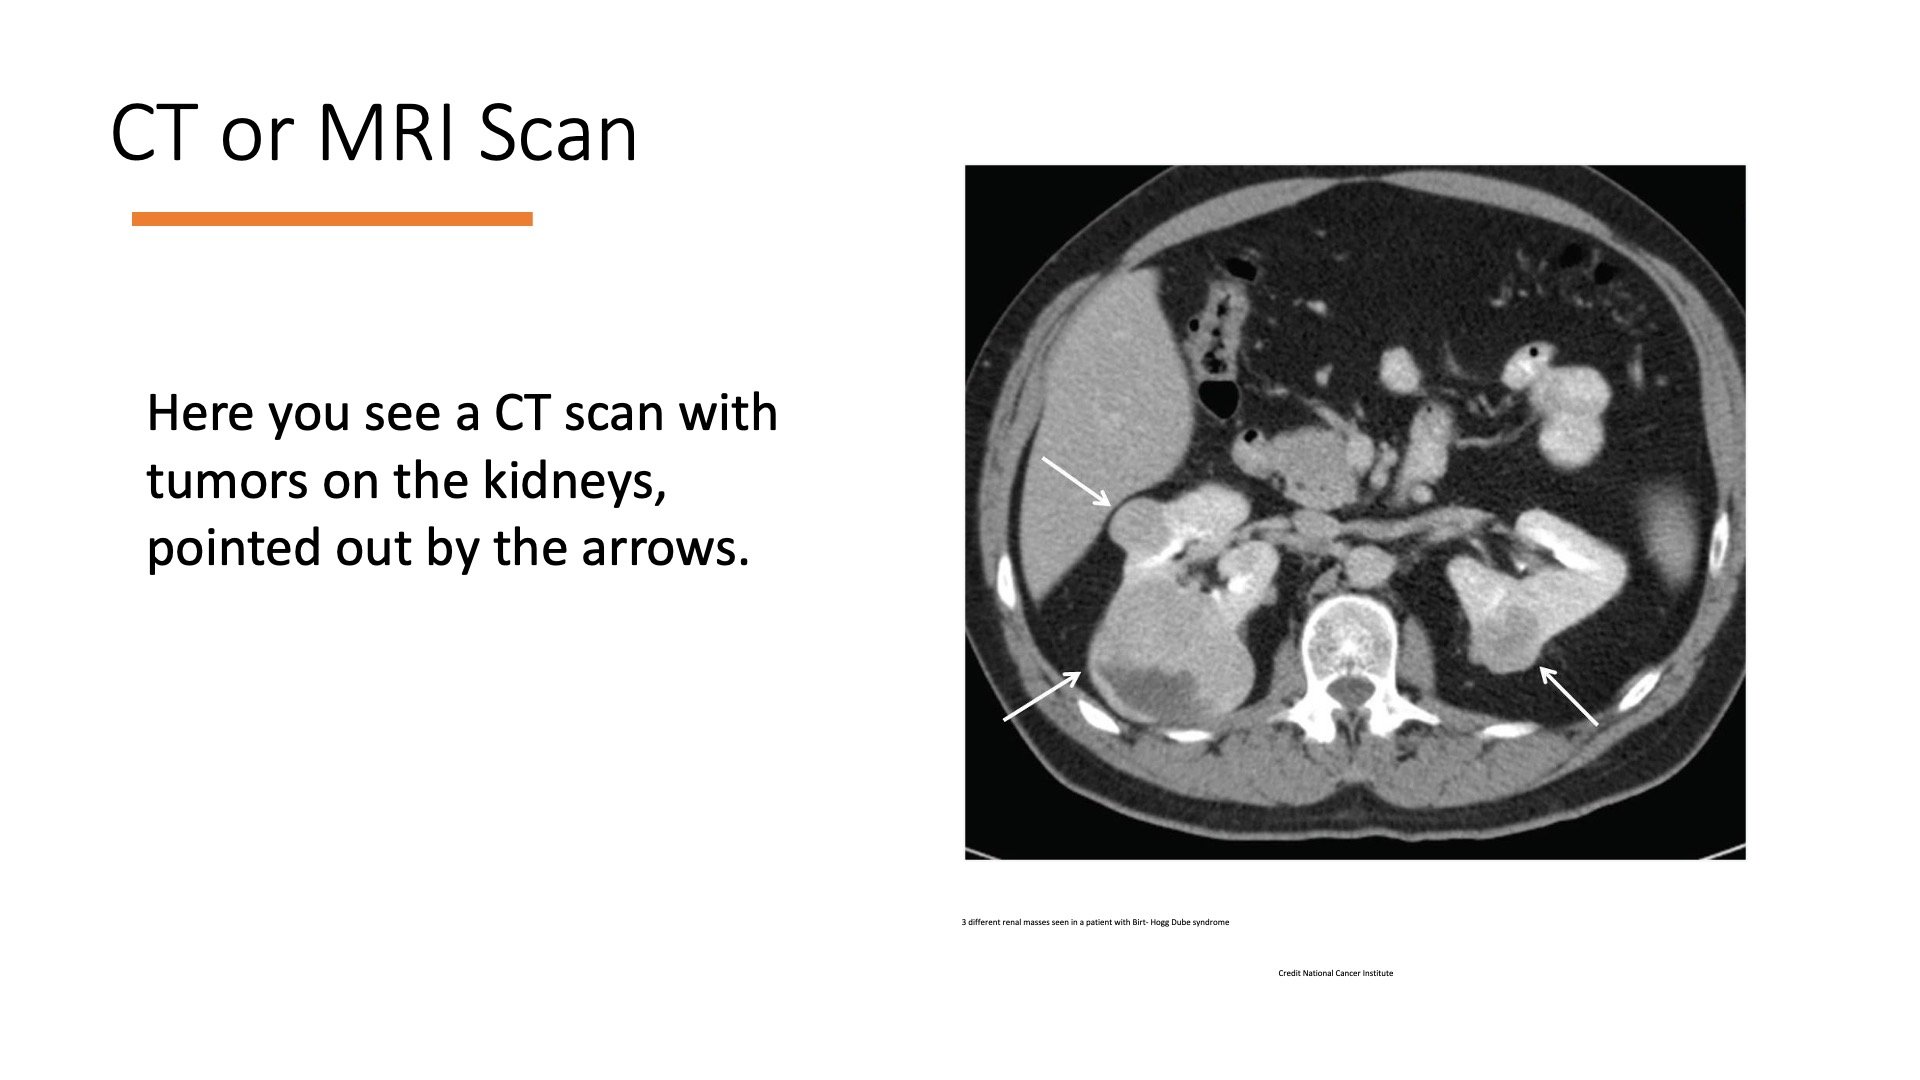

A radical nephrectomy is most often need for kidney cancer treatment. When the mass in the kidney is either too large or in a position where it can’t be separated from the kidney, the entire kidney, surrounding fat, and sometimes the adrenal gland are removed.